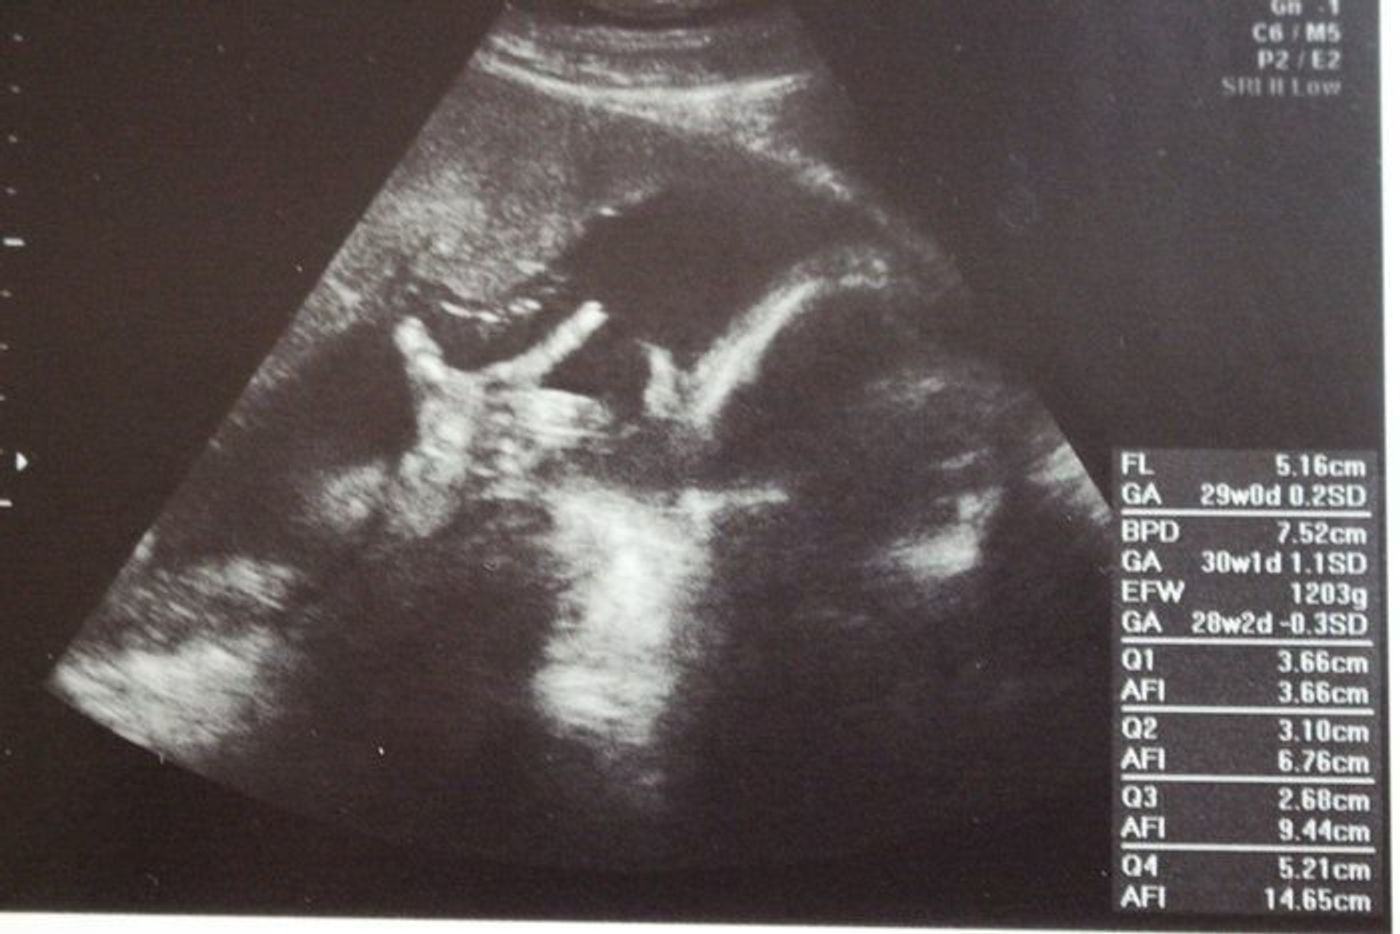

エコーの写真の口元も開いてますよね(^^) 妊娠後期 28週6日 胎児1447g BPD784 AC23 FL544 ママ555kg 逆子体操と、赤ちゃんへの声かけの効果あってか、 この日から赤ちゃんの頭は下向きになっていました。 妊娠4週目胎児の状態と妊婦の変化は?流産の可能性は?体験談も yotsubaよつば 妹の妊娠、ときどき私。~4話 エコー写真の見方がわからない!~ 生理のことから妊娠・出産・育児まで。女性のための 医療監修妊娠4ヶ月目の妊婦と胎児の様子。